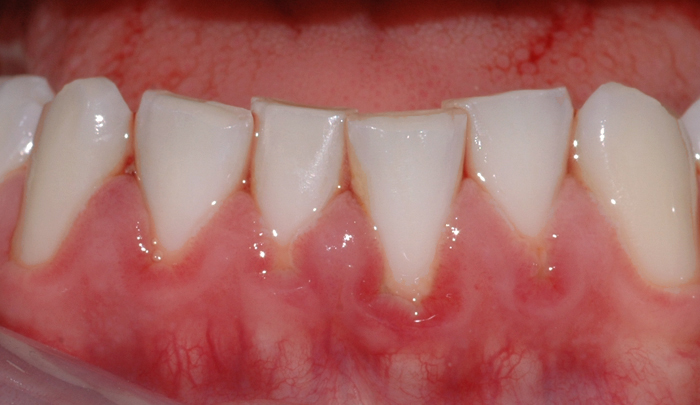

Et friskt tannkjøtt har lys rød farge og ligger stramt inntil tennene (fig. I). Et betent tannkjøtt får en mørkere rødfarge, det blir hovent og kan føles ømt ved berøring. Videre vil man kunne oppleve at tannkjøttet blør ved rengjøring og at det ligger mindre stramt inntil tennene.

Fig 1: Et friskt tannkjøtt har lys rød farge og ligger stramt inntil tennene Fig 2: Mangelfullt renhold kan over tid føre til utvikling av gingivitt

Mangelfullt renhold kan over tid føre til utvikling av gingivitt. Dette skyldes bakterier og mykt belegg (plakk) som blir liggende på tannen i kontakt med tannkjøttet (fig. II). Om man har mye tannstein, vil også dette kunne medvirke til utvikling av gingivitt. Gingivitt oppstår lettest mellom tennene og ellers der det er vanskelig å holde rent.